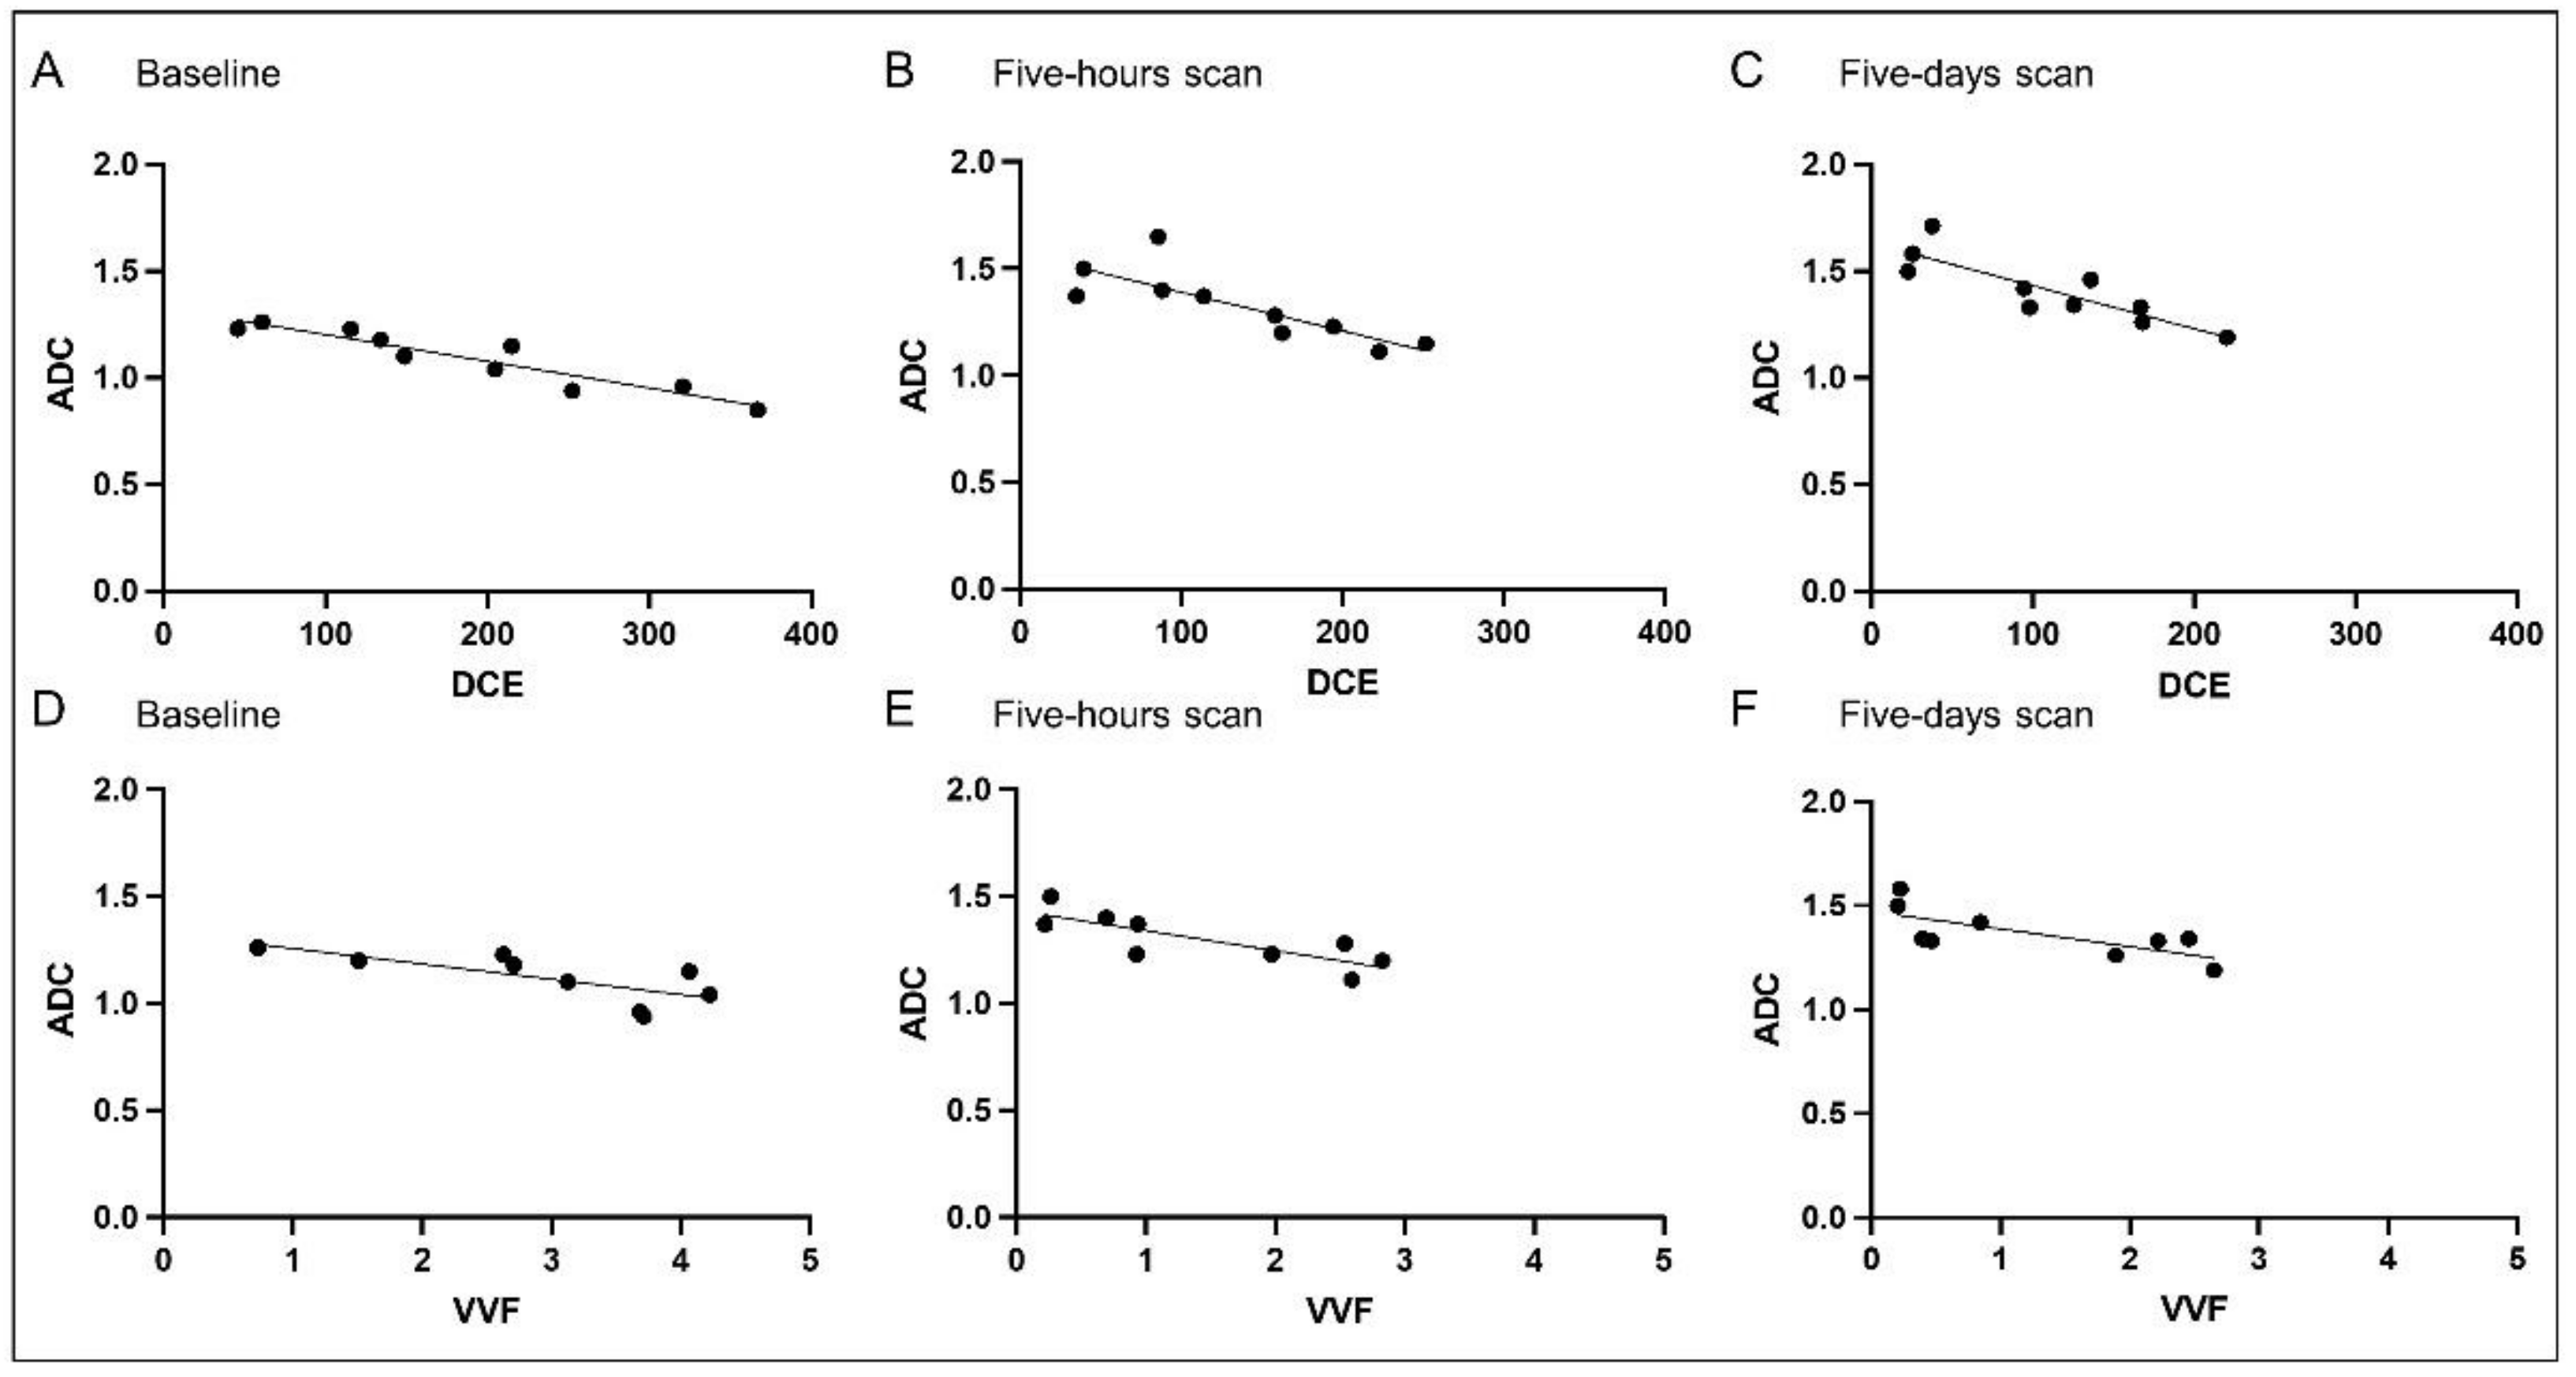

3.2. Correlation Analysis